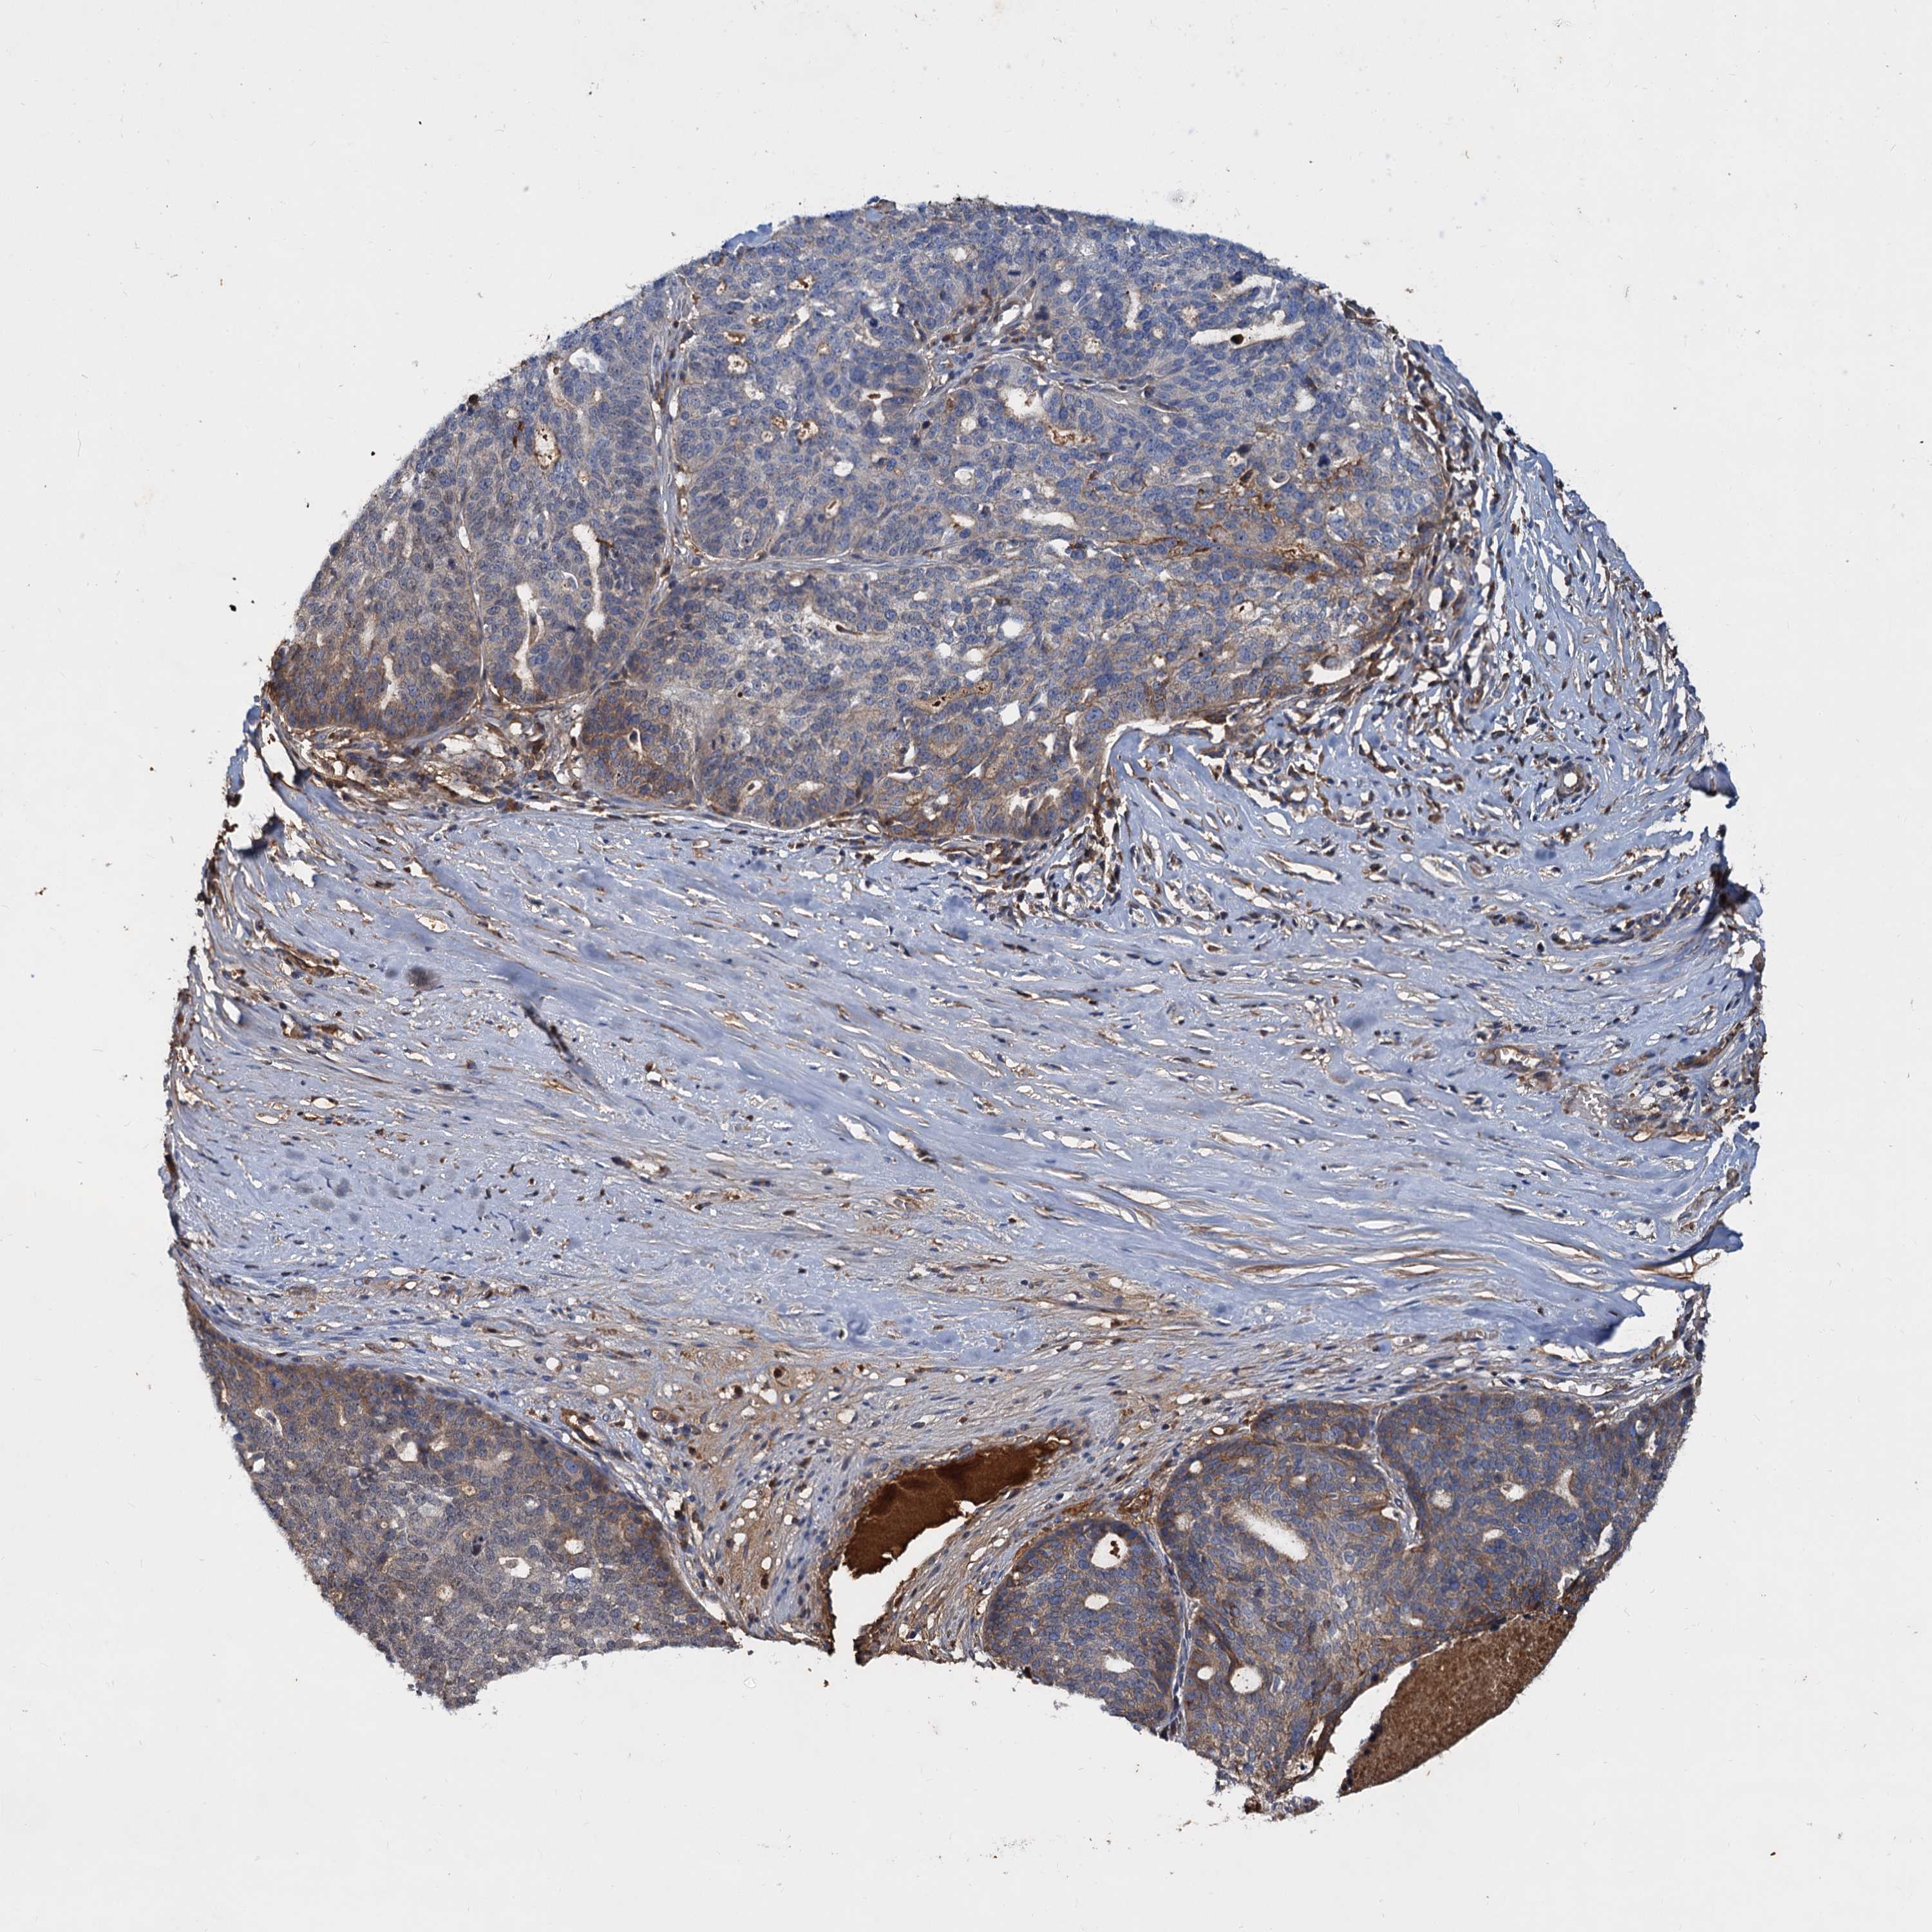

OVARIAN CANCER - Protein expressioni

A mouse-over function shows sample information and annotation data. Click on an image to view it in a full screen mode. Samples can be filtered based on level of antibody staining by selecting one or several of the following categories: high, medium, low and not detected. The assay and annotation is described here.

Note that samples used for immunohistochemistry by the Human Protein Atlas do not correspond to samples in the TCGA dataset.

Antibody stainingi

Antibody staining in the annotated cell types in the current human tissue is reported as not detected, low, medium, or high, based on conventional immunohistochemistry profiling in selected tissues. This score is based on the combination of the staining intensity and fraction of stained cells.

Each image is clickable and will lead to virtual microscopy that enables deeper exploration of all samples and also displays staining intensity scores, fraction scores and subcellular localization as well as patient and tissue information for each sample.

Antibody HPA035827

Staining

High

Medium

Low

Not detected

Intensity

Strong

Moderate

Weak

Negative

Quantity

>75%

75%-25%

<25%

None

Location

Nuclear

Cytoplasmic/membranous

Cytoplasmic/membranous,nuclear

Cystadenocarcinoma, serous, NOS

Carcinoma, endometroid

Cystadenocarcinoma, mucinous, NOS

Carcinoma, NOS